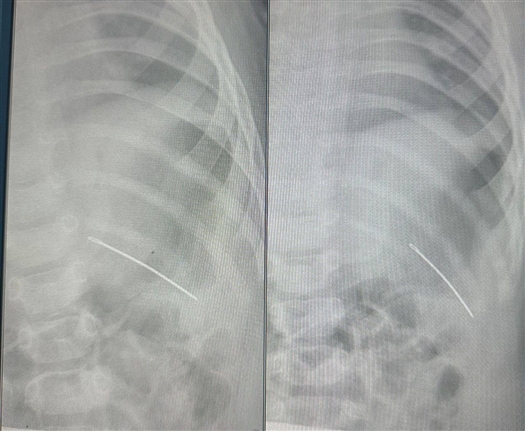

По рентгену ключицы и тазобедренного сустава стало видно, что в грудной клетке ребенка находится инородное тело — швейная игла. Случай оказался непростым: возможно, в результате падения игла вошла чрез кожу снаружи, проткнув насквозь ребро. В результате у девочки оказались затруднены движения левыми рукой и ногой.

Врачи оперативно приняли решение об операции и безопасно удалили инородное тело.

Детский хирург областной клинической больницы Дмитрий Быков отметил, что если бы игла оказалась на 2 см выше, она могла бы попасть в сердце, что создало бы непосредственную угрозу для жизни.